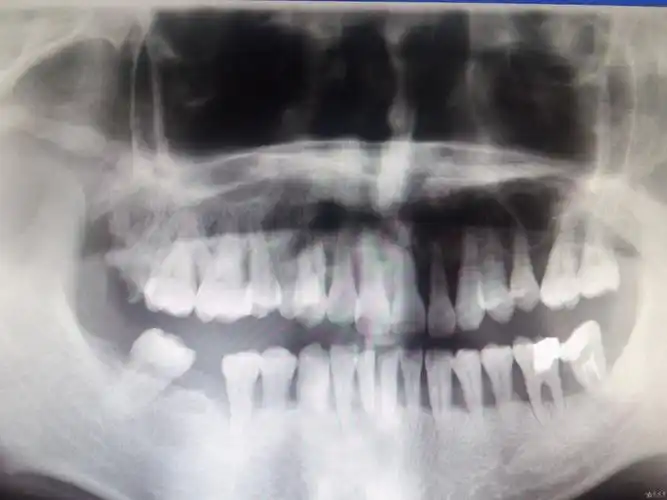

进来了就发一个牙片纪念一下我两个全包围横向阻生牙